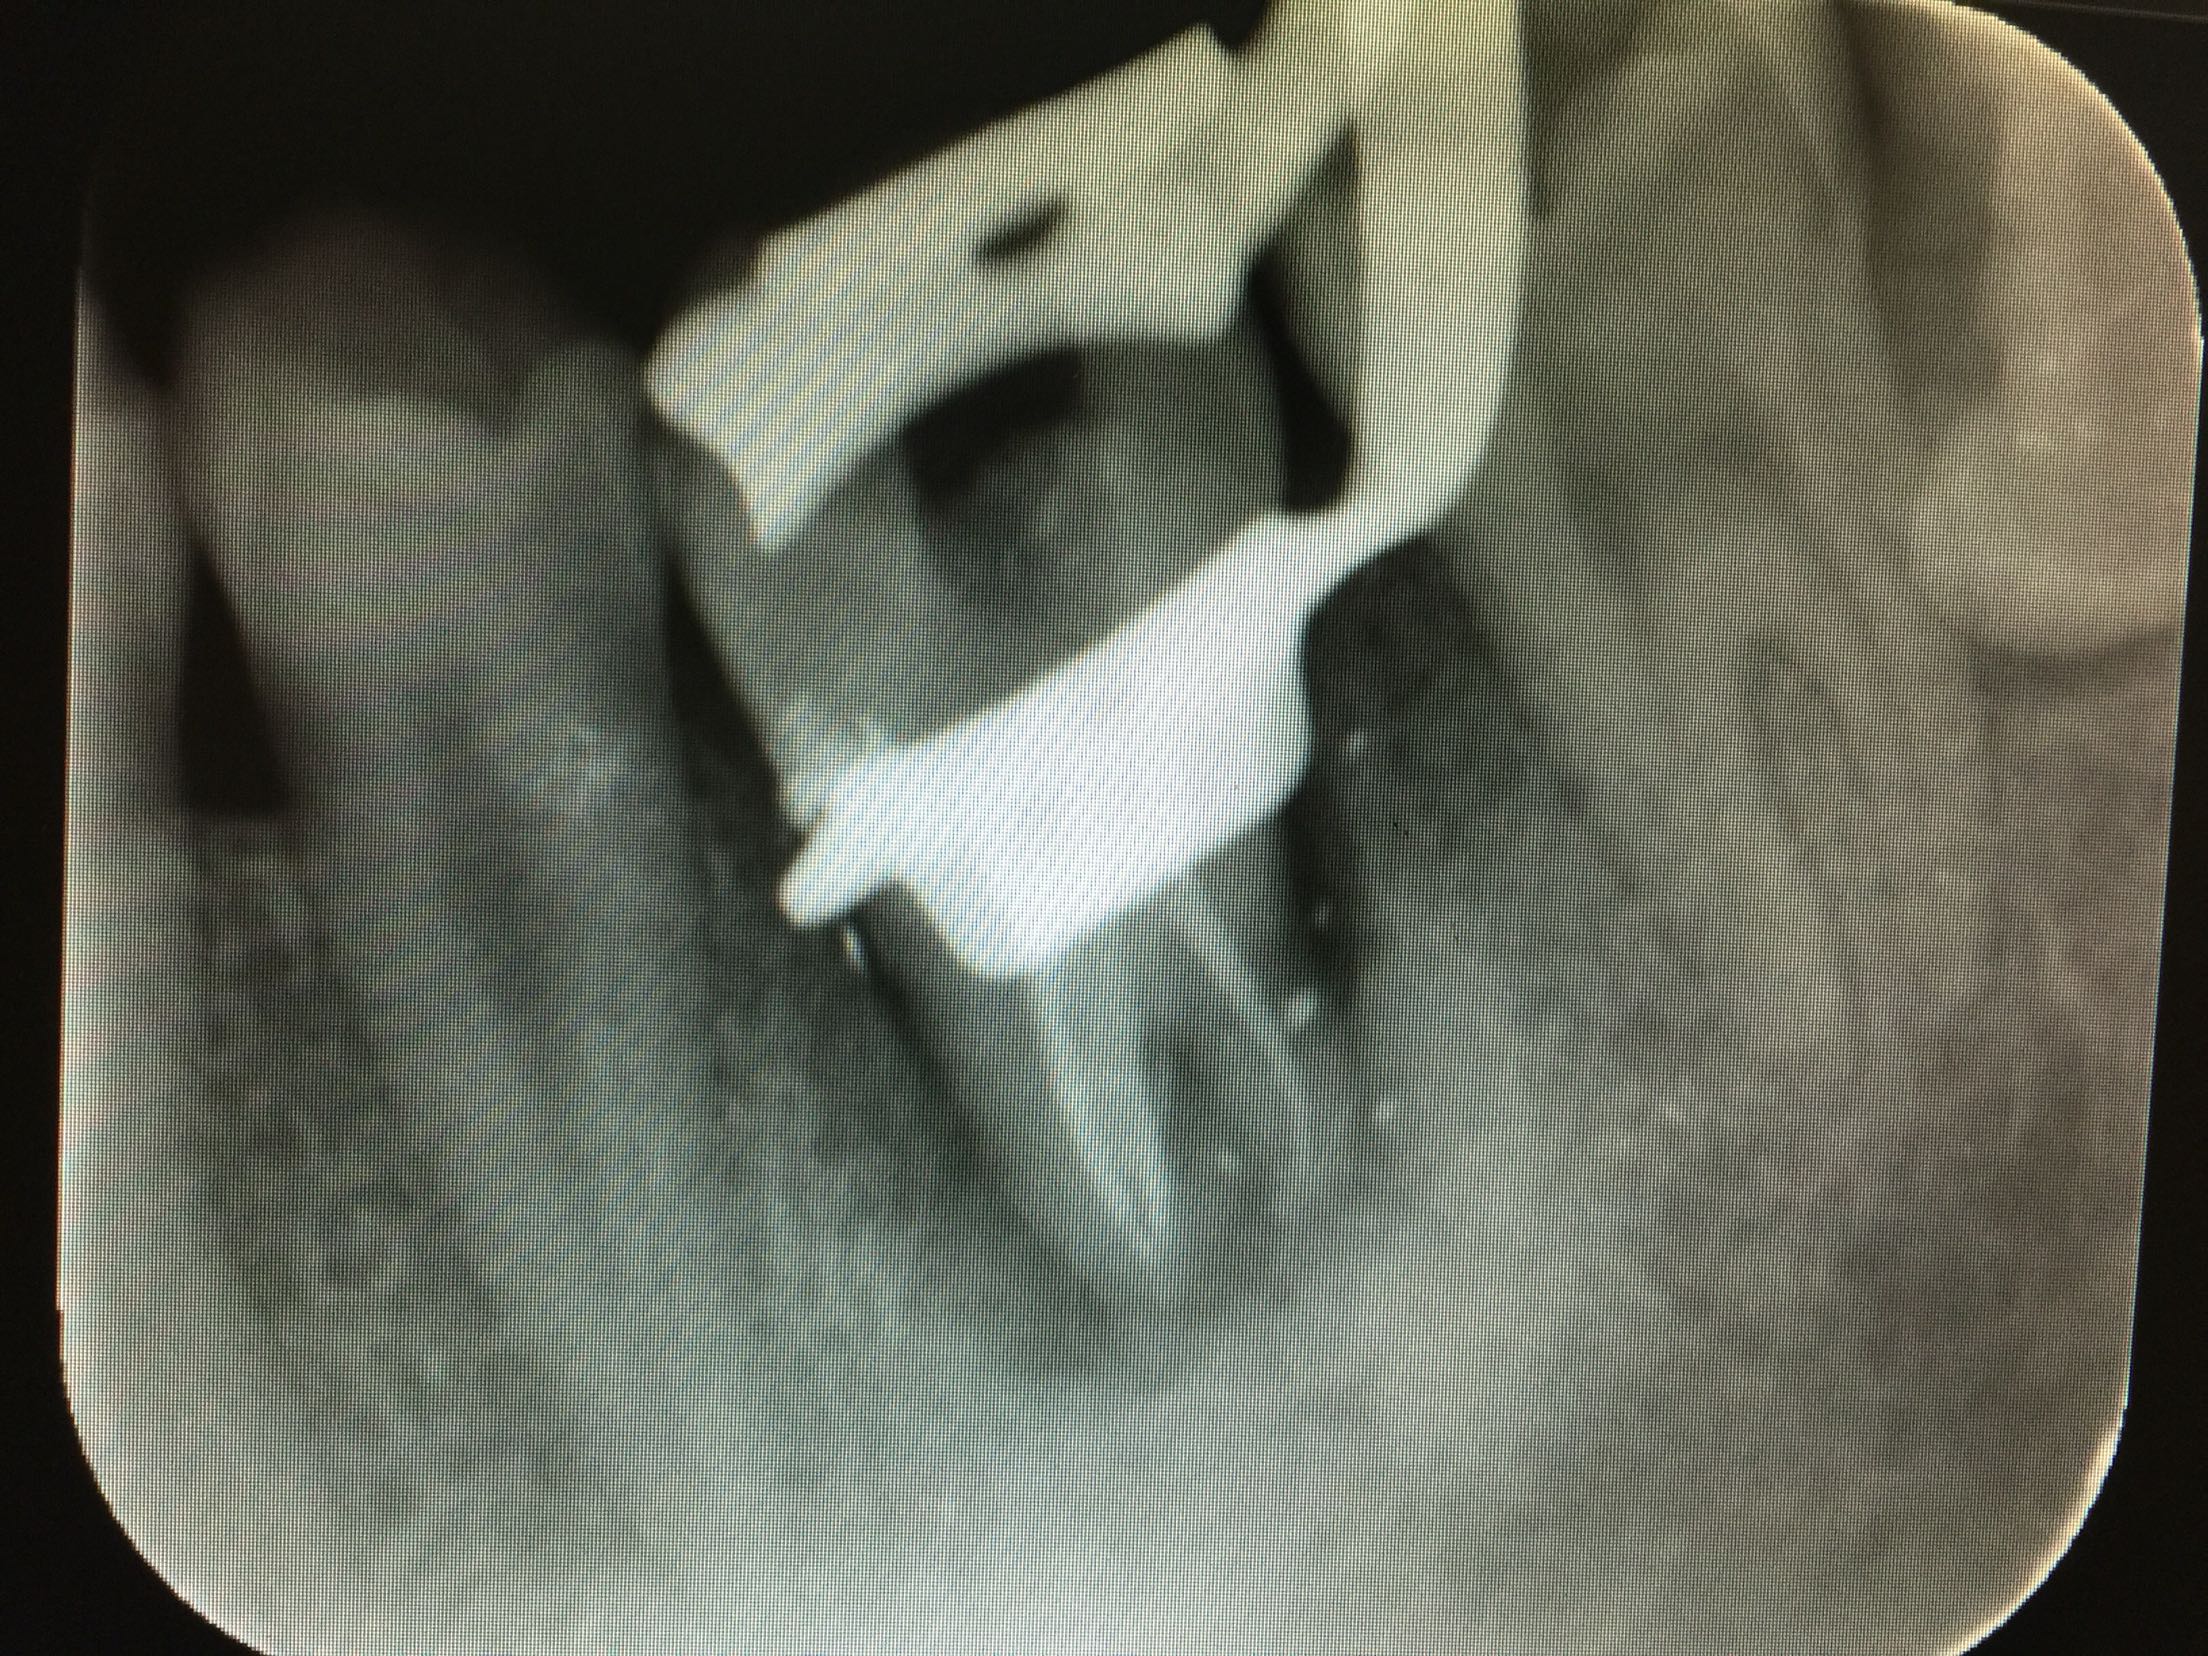

碧蓝麻局部浸润,36(48)牙开髓揭髓顶,探查根管3根,牙髓摘除术,k挫初步预备,根管测长仪测量根管长度,各根管内导入根管润滑剂EDTA,Protaper镊钛器械预备根管,冲洗,超声荡洗,水溶性氢氧化钙充填根管,暂封,约复诊。 复诊:一周后,诊间无不适,36牙暂封完好,冷-,探-,叩-,不松。 试主尖

根充